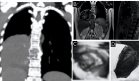

La resonancia magnética nuclear (RMN) con contraste de la columna dorsal mostró alteración en la intensidad de la señal de la médula espinal a nivel cervical inferior, lo que condujo a estudios complementarios. El mismo día, el paciente ingresó a otra clínica por sospecha de mielitis transversa, con síntomas de dolor punzante en la columna torácica, hemiparesia izquierda predominante en el miembro superior, dificultad respiratoria leve, hiporreflexia y pérdida de 2 kg de peso en una semana.

Una nueva resonancia magnética de la columna cervical confirmó una mielitis transversa longitudinalmente extensa (LETM). Se inició tratamiento con metilprednisolona en pulsos intravenosos de 1 g cada 24 horas durante 5 días. Los síntomas se resolvieron sin reacciones adversas, permitiendo el alta hospitalaria el 27 de febrero de 2017. En abril de 2017, ante la persistencia del realce con gadolinio en la RMN cervical, se administró un nuevo ciclo de metilprednisolona.

Los criterios diagnósticos de NMOSD incluyen la presencia de neuritis óptica, mielitis aguda con LETM y síndrome del área postrema. En este caso, el paciente cumplió con los criterios diagnósticos al presentar LETM confirmada por RMN y anticuerpos anti-AQP4 positivos en LCR. La exclusión de esclerosis múltiple se realizó con base en la ausencia de lesiones cerebrales típicas en RM.